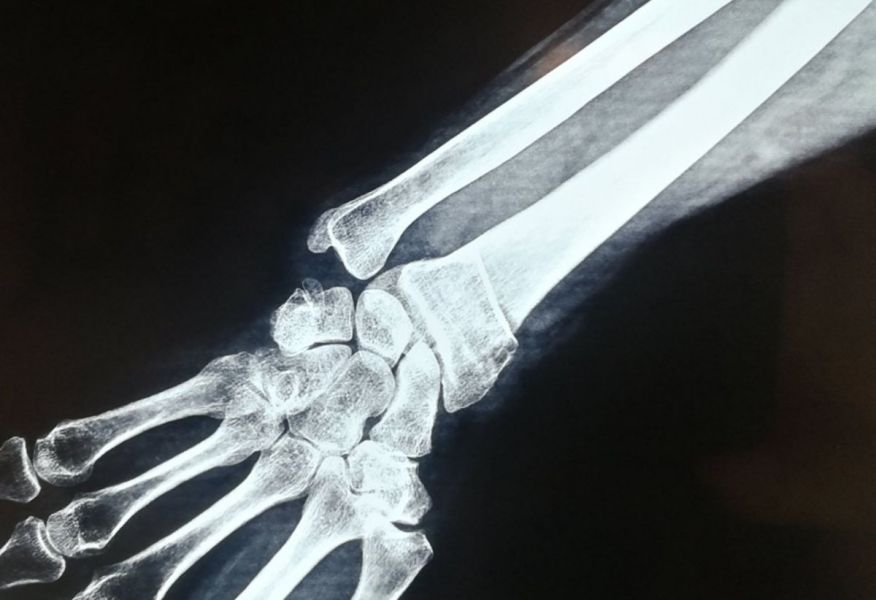

4. Displaced fracture of distal end of the right radius (wrist fracture) in a 63-year-old female.

Treatment. Open reduction internal fixation

I. Before operation, anteroposterior x-ray of the wrist II. Before operation, lateral x-ray of the wrist IIA. Day of procedure, lateral view IIB. Day of procedure, anteroposterior view